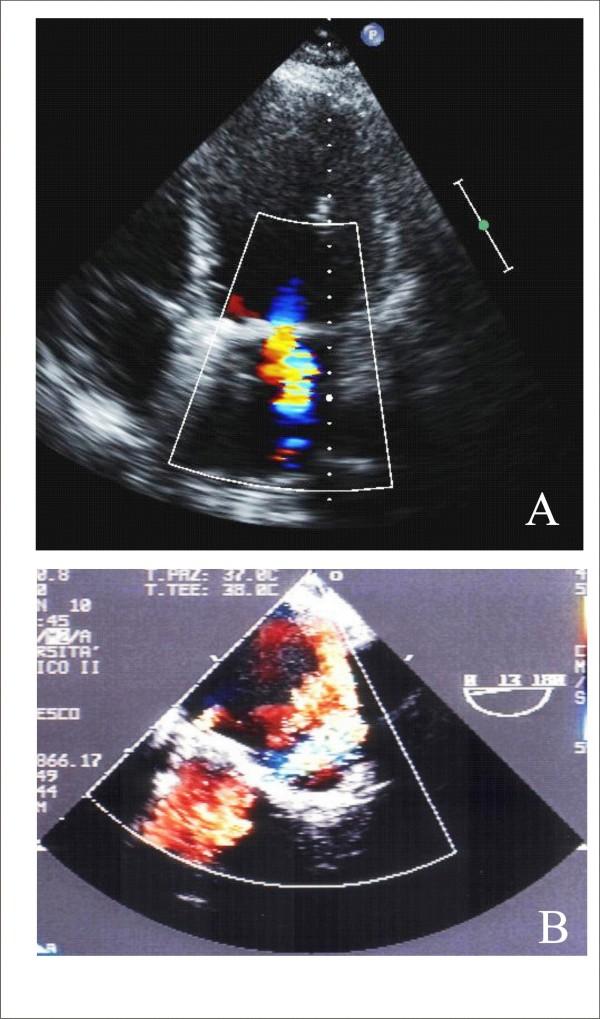

Aortic stenosis and mitral regurgitation, patent foramen ovale, interatrial septal defect, atrial fibrillation and perivalvular leak, are now amenable to percutaneous treatment. These percutaneous procedures require the use of Transthoracic (TTE), Transesophageal (TEE) and/or Intracardiac echocardiography (ICE). This paper provides an overview of the different percutaneous interventions, trying to provide a systematic and comprehensive approach for selection, guidance and follow-up of patients undergoing these procedures, illustrating the key role of 2D echocardiography.

主动脉瓣狭窄、二尖瓣反流、卵圆孔未闭、房间隔缺损、心房颤动及瓣周漏,目前均适合经皮治疗。这些经皮手术需要使用经胸超声心动图(TTE)、经食管超声心动图(TEE)和/或心内超声心动图(ICE)。本文概述了不同的经皮介入治疗,试图为接受这些手术的患者提供一种系统、全面的选择、指导及随访方法,并阐述二维超声心动图的关键作用。